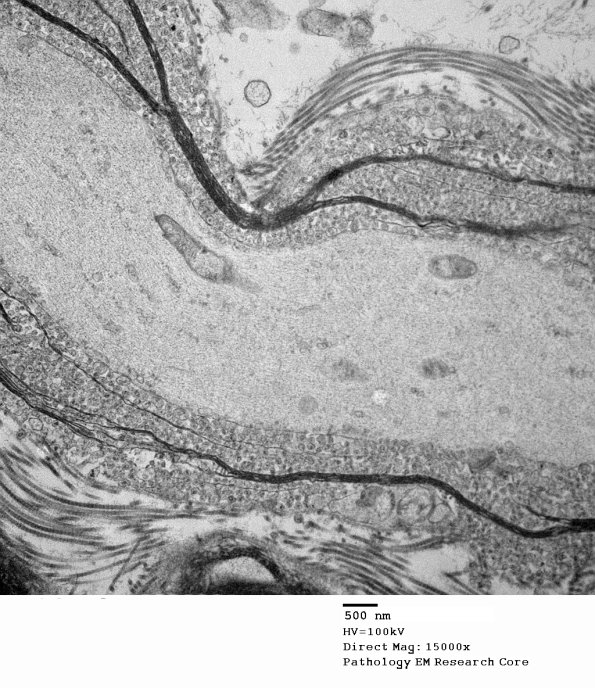

19C2 Artifact, vesicular myelin, spinal root EM 023A - Copy

Higher magnification of image #19C1. (electron micrograph)